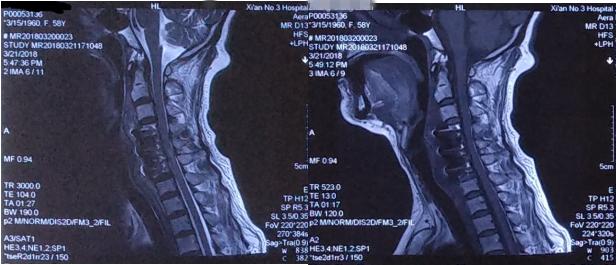

术后颈椎正侧位X片